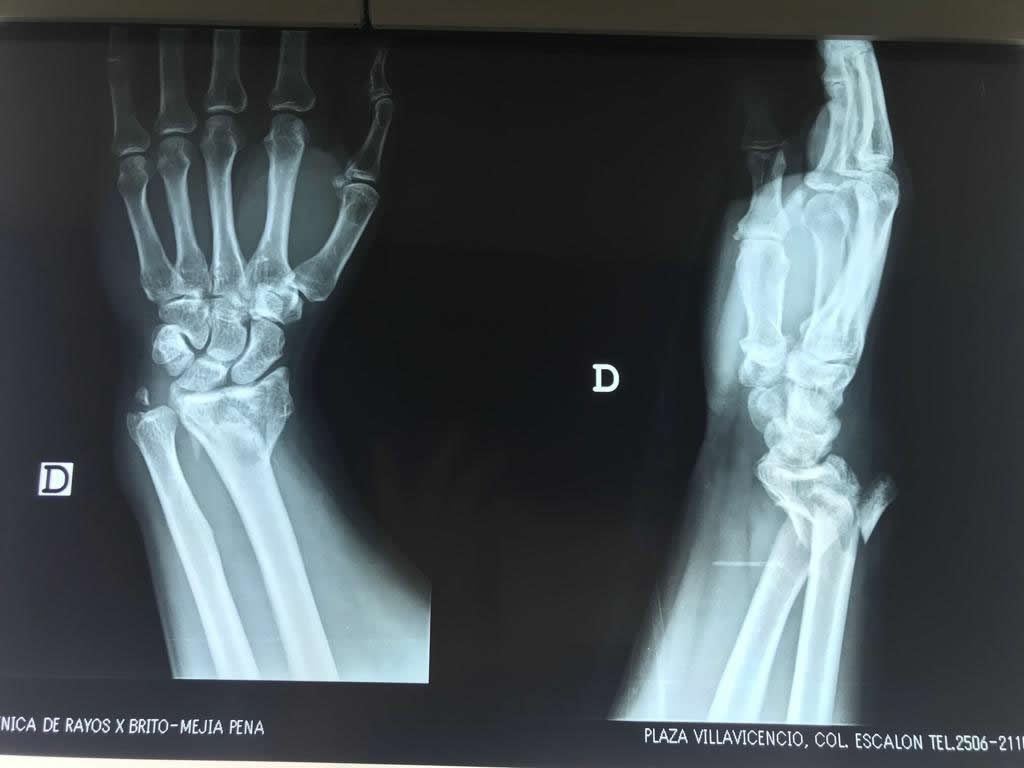

Cirugías de Codos - Cirugías de Muñecas y Manos

Los procedimientos más comunes en cirugía de la mano son aquellos destinados a reparar traumatismos, incluyendo lesiones de tendones, nervios, vasos sanguíneos, y articulaciones; huesos fracturados; y quemaduras, cortes, y otros daños de la piel.